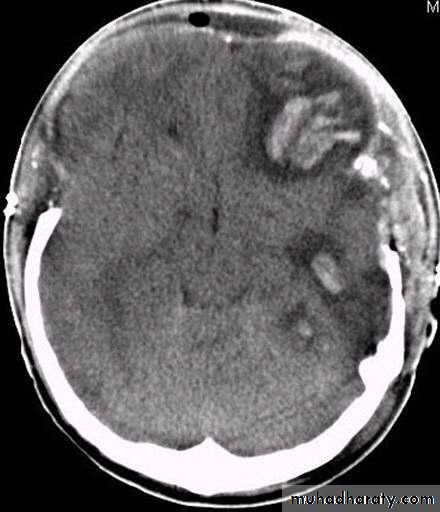

Clinical Picture: patient will present with a picture similar to that of an extradural haematoma, but there is persistent loss of consciousness with no lucid interval.Ct scan will show a concave hyperdence collection because blood follows the subdural space over the convexity of the brain.

Acute Subdural Haematoma are rapidly evolving lesions and early evacuation via craniotomy is mandatory.

Acute Subdural Haematoma